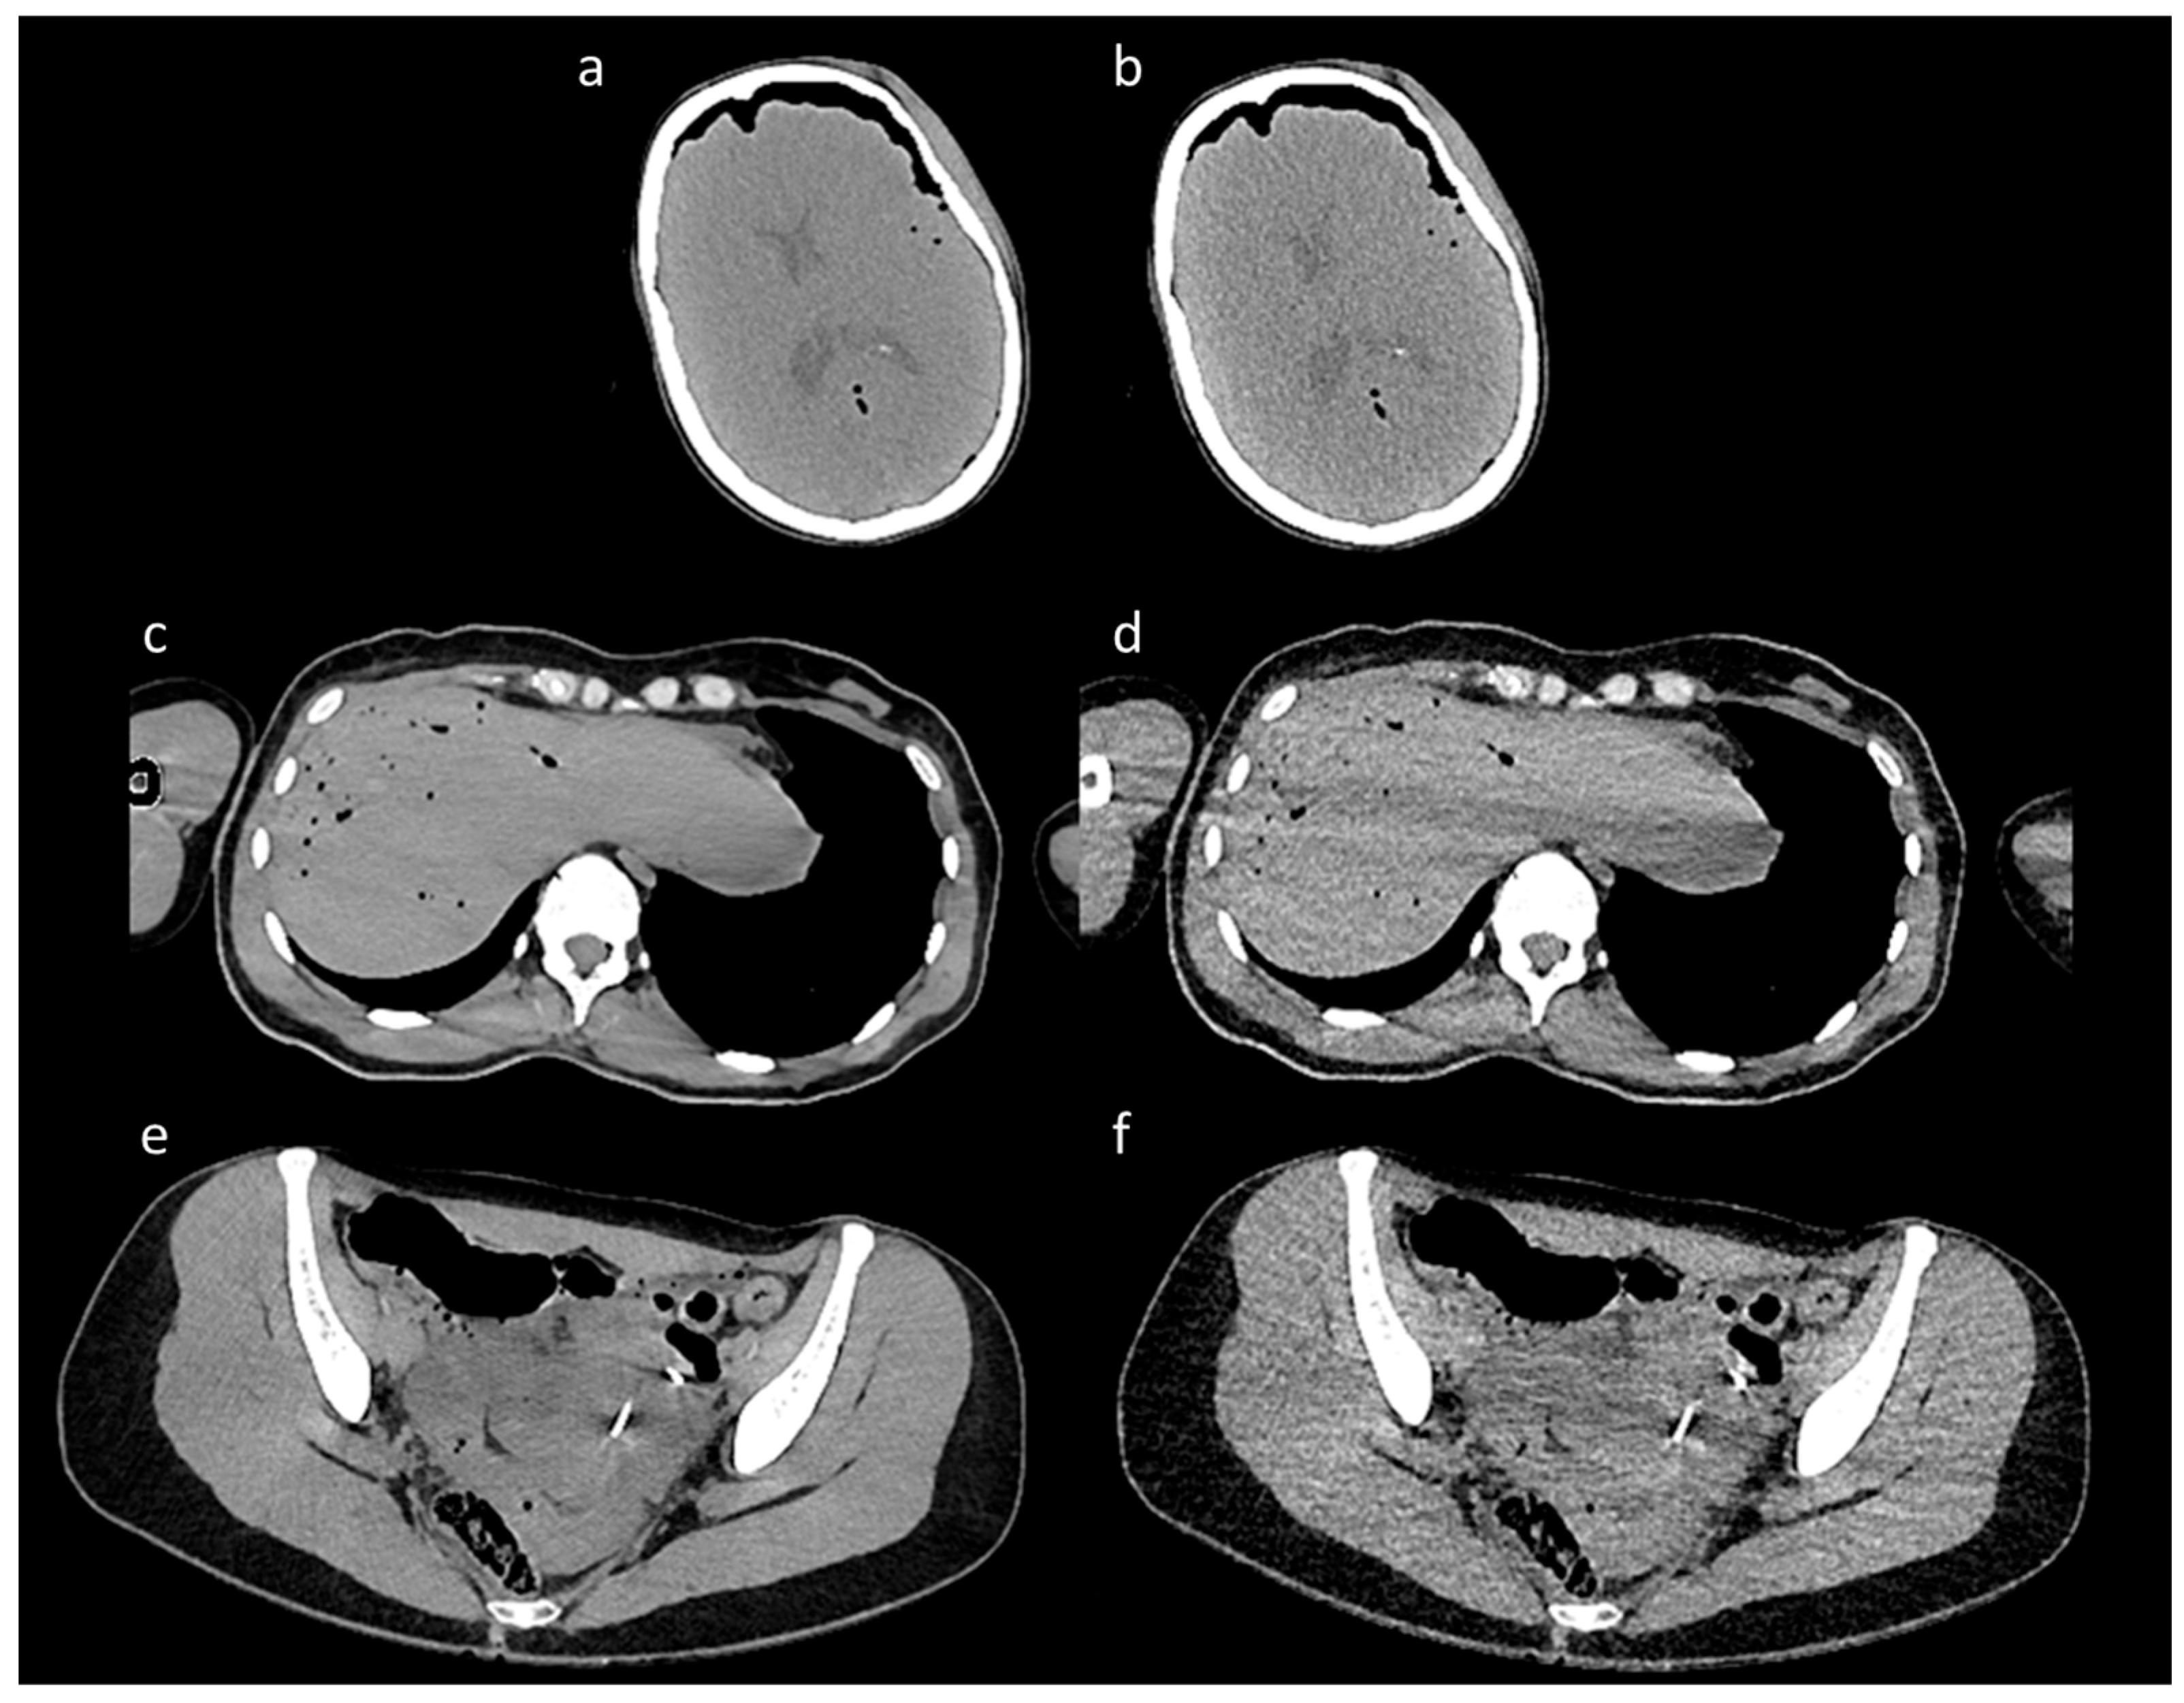

The scans encompassed a range of body dimensions representative of diverse patient anatomies, with heights ranging from 142 cm to 204 cm and varying body compositions, including a broad spectrum of body mass indices (BMI 18–32). The CT images were reconstructed using the Iterative Reconstruction technique, generating pairs of high-quality (HQ) and low-quality (LQ) images for each scan (Figure 1). Specifically, low-dose (LQ) scans exhibited significant noise levels, while high-dose (high-quality) scans served as a reference standard with low noise.

Figure 1.

Representative paired CT images from the training set. The figure shows a representative selection of paired CT images from the training dataset. The figure is organized into three pairs, each featuring a high-dose image and its corresponding low-dose counterpart. The high-quality images, shown in panels (a,c,e), served as clean reference targets for the model, while the LD images in panels (b,d,f) were used as noisy inputs. The paired images come from three distinct anatomical regions: (a,b) show a scan of the skull, (c,d) show a scan of the abdomen at the level of the liver, and (e,f) illustrate a scan of the pelvis.

Each CT scan produced approximately 3300 images, with slice thicknesses of 0.6 mm and a spatial resolution of 512 × 512, equally divided between HQ and LQ. The mean value of dose reduction in the LQ scans was 55% (minimum 41%–maximum 83%), allowing a significant decrease in X-ray exposure without compromising the detail and contrast scale of the images for diagnostic analyses.